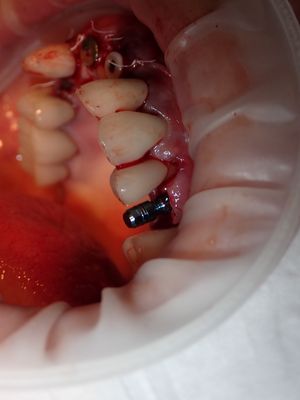

NSankhyan - immediate 13, impls 1121 and 25 with grafting

13 exo, loss of labial plate, implant placed buccal region grafted with sticky bone and collagen membrane soaked in prf fluid. 11/21 limited Labial-palatal width of bone, ridge split to 5mm, osteotomies prepared to about 2mm, remainder with densah drills, implants placed with ample bone, buccal grafted with same sticky bone. densah drills used for apical portion of 25 implant, soft bone, implant placed